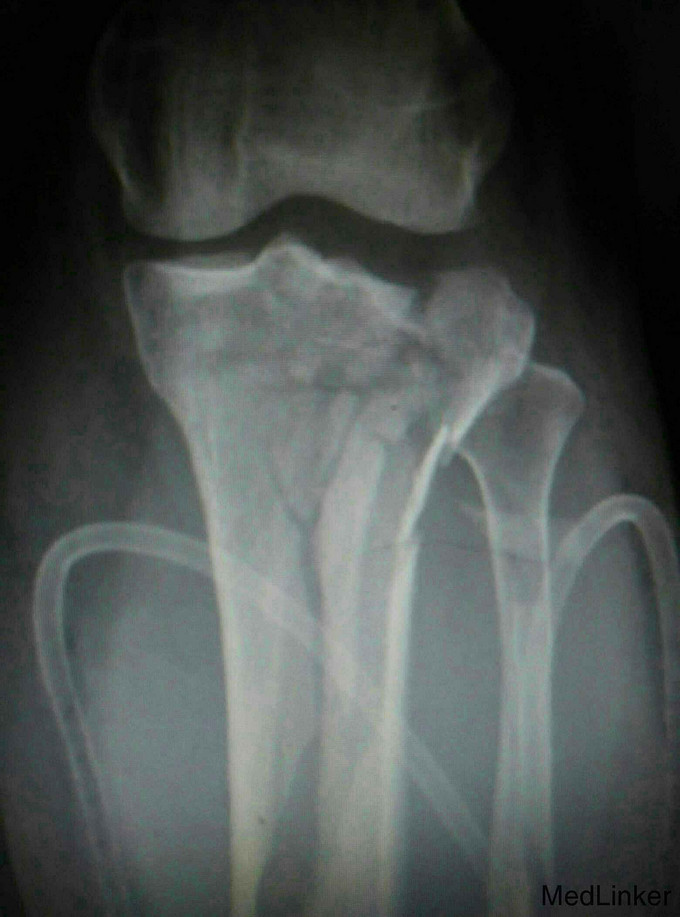

车祸伤致左膝部肿痛,活动受限4小时

入院查体局部肿胀明显,足背动脉搏动减弱,末梢血运及皮肤感觉减弱,触诊见局部肿胀明显,呈板状,无弹性。入院完善X线片及CT扫描等检查,同时做了下肢彩超提示无血管损伤及栓塞。